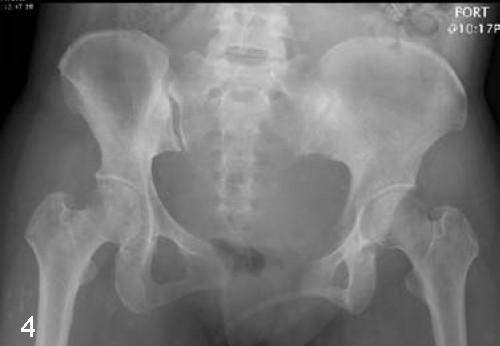

耻骨移位:会出现长短腿以及影响步态(有很多产妇的步态足部的承重偏小指侧、大拇指没有推进、产后依然双脚足部过度外八)

耻骨变形:会有骨盆偏转,影响髋关节灵活度,出现骨盆旋转,导致腰椎变形,出现腰痛。

腰椎为中心,骨盆左右两边的宽度不等